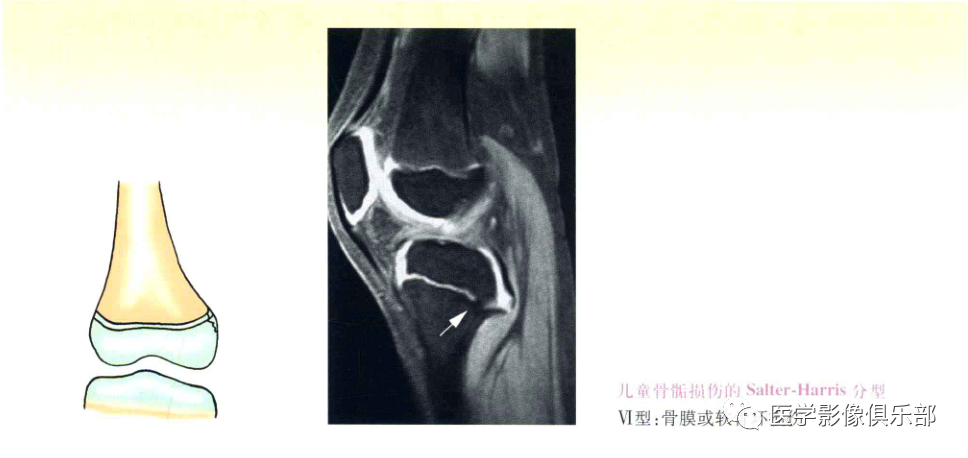

Ⅵ型:骨膜或软骨环(骺板周围环)损伤,较少见。